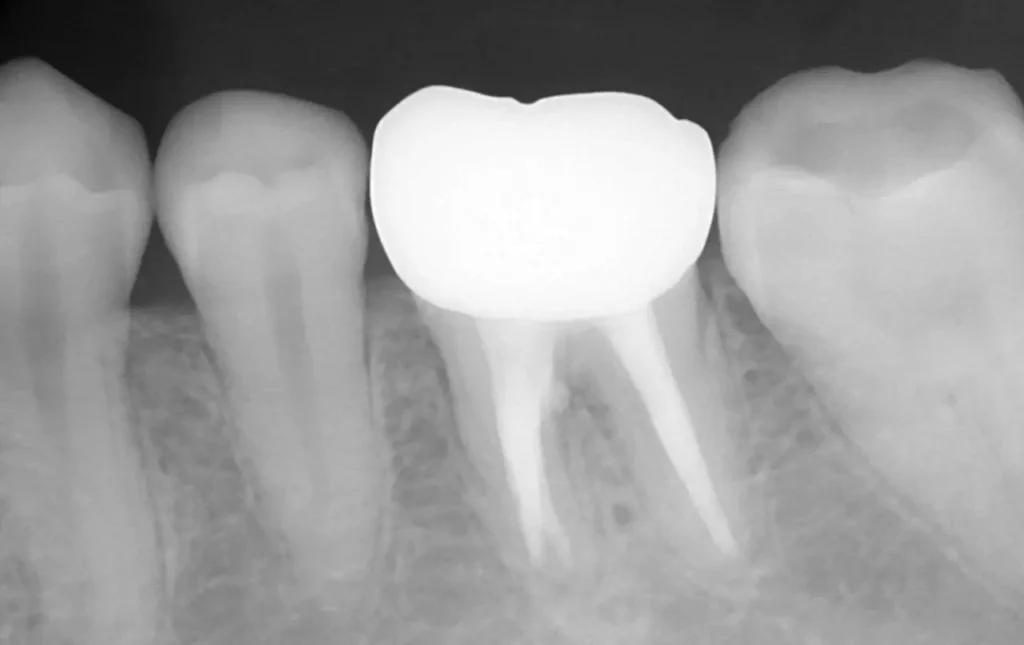

初診時

管の分かれている部分に根の治療による穿孔がありました

術中

穿孔部分の封鎖と通常の根管治療を行いました

術後

症状は、完全に消えて、穿孔部分の封鎖と確実な清掃、充填が確認できます